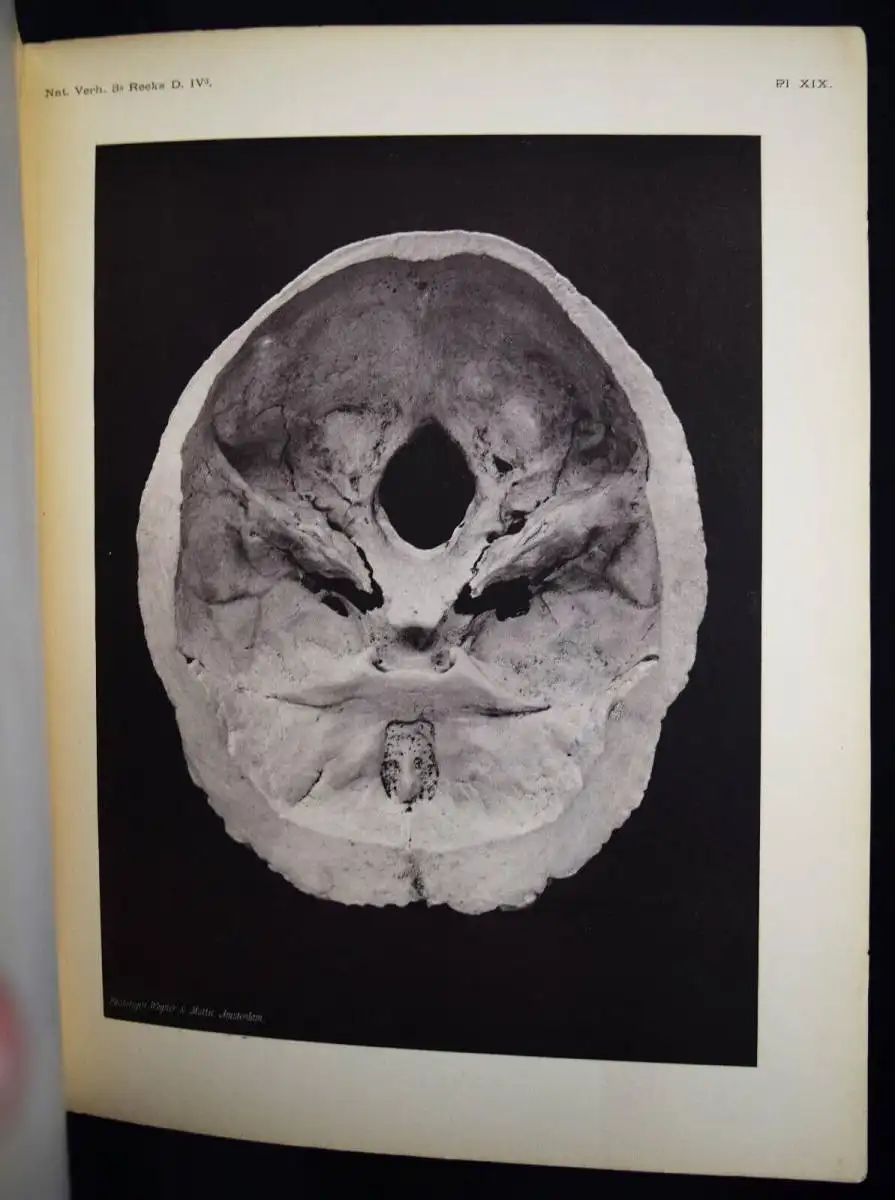

Un cas de Leontiasis ossea (Craniosclerosis). Haarlem, Erven Loosjes

1883. 4°. 27 S. u. 6 Tafeln nach Fotografien in Heliogravure. Pbd. der

Zeit. (Natuurkundige Verhandelingen van den Hollandsche Maatschappij der

Wetenschappen, 3de Verz., Deel IV, 3de Stuk.).

Hirsch/Hüb. II, 373 ff. – Sehr

seltene erste Ausgabe der interessanten Arbeit über das

Krankheits-Symptom Leontiasis (dt. Löwenitis, Löwengesicht oder

Löwengesichtssyndrom) bei welcher Wucherungen der Gesichts- und

Schädelknochen zu einem löwengesichtsähnlichen Aussehen führen. Sie

entsteht als Komplikation einer renalen Osteodystrophie. Die von Wagner

& Mottu in Amsterdam in Phototypie hergestellten Tafeln zeigen einen

präparierten Kopf und einen Schädel. Sie sind ein frühes Beispiel für

die Verwendung der Fotografie in der Wissenschaft. – Der niederländische

Mediziner C. E. Daniels (1839-1909) war Prof. in Amsterdam.